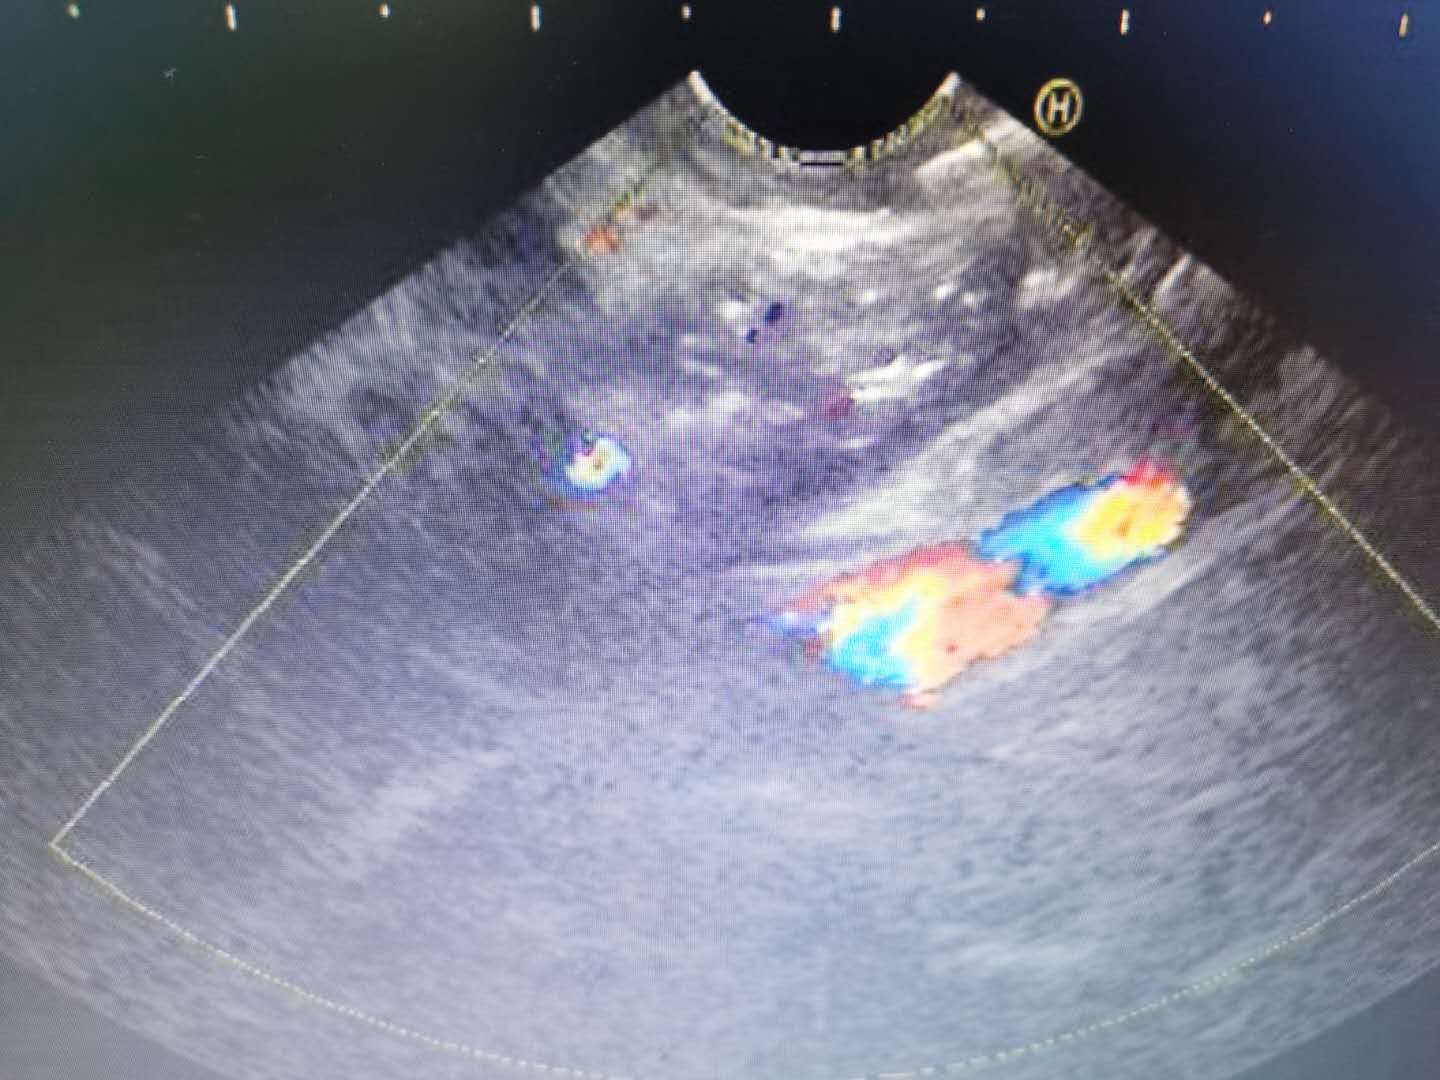

48岁的王先生就是一位胰腺癌患者,每天都在癌痛的折磨中煎熬,即使频繁使用*啡吗**等镇痛药物,仍然痛不欲生。*安泰**市中心医院肝胆胰腺内科主任袁海鹏了解到王先生的情况后,立即组织科室讨论,制定治疗方案,在征得王先生及其家属的同意后,袁海鹏为患者实施了*安泰**市首例超声内镜引导下腹腔神经节阻滞手术(EUS-CPN),整个过程仅耗时15分钟。术后,王先生未再出现严重疼痛,对生活及下一步治疗产生极大信心,本人及家属对治疗效果十分满意。

【医学链接】什么是超声内镜引导下腹腔神经节阻滞术呢?首先需要了解腹腔神经节,它位于膈肌下端后腹膜内,围绕腹腔干和肠系膜上动脉,位置恒定,功能就是传递来源于上腹部,包括胰腺、肝脏、胆囊、胃等脏器的疼痛,然后向脊髓相应节段投射,上达中枢,产生痛感。因此,阻断腹腔神经节可以有效缓解癌痛。超声内镜在胃内能清晰显示腹腔动脉干及毗邻结构,准确定位神经节,并通过细针穿刺向神经节注射化学药物而起到阻滞神经,缓解疼痛的作用,既往多项研究证明该方法安全有效,可明显提高癌症晚期病人的生活质量。